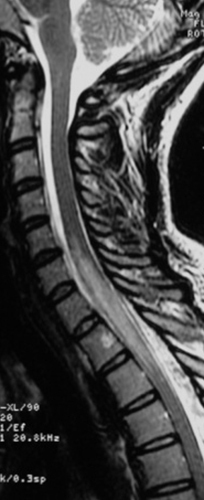

De plus, sa sœur vous rapporte des troubles de la marche qui semblent évoluer depuis le début du mois de février 2019.

À l’examen clinique : la patiente est désorientée. Elle a une amputation dans les hémichamps visuels gauches des deux yeux. Le testing moteur vous semble légèrement plus faible aux deux membres inférieurs, vous ne parvenez pas à évaluer la sensibilité. Ses réflexes ostéo-tendineux sont vifs aux membres inférieurs, vous retrouvez une extension lente des deux hallux lorsque vous effleurez la plante des pieds avec votre marteau. Lorsque vous regardez les chaussures de la patiente, il vous semble que l’avant de ses chaussures est très abîmé par rapport à l’arrière.